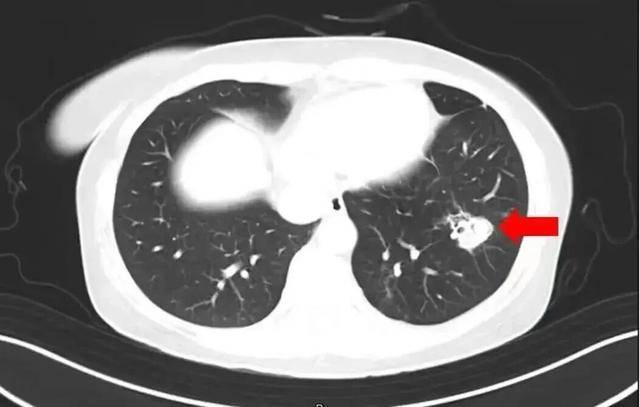

近日,一6岁女童因持续发烧17天且意识不清,被转至郑州郑大一附院治疗。医生检查后大吃一惊:孩子脑子竟被“啃”出大大小小十几个洞,再晚来几天可能会被“啃空”。抽取洞内积液检测后,医生锁定了“真凶”——烟曲霉菌。

2025年1月,江苏扬州的张大爷为迎接春节开始大扫除,清扫过程中不慎吸入大量灰尘和霉菌孢子,导致哮喘发作。张大爷随即服用了常备的哮喘治疗药物,可症状反而逐渐加重。经检查,张大爷的肺部出现感染,确诊为肺曲霉病。